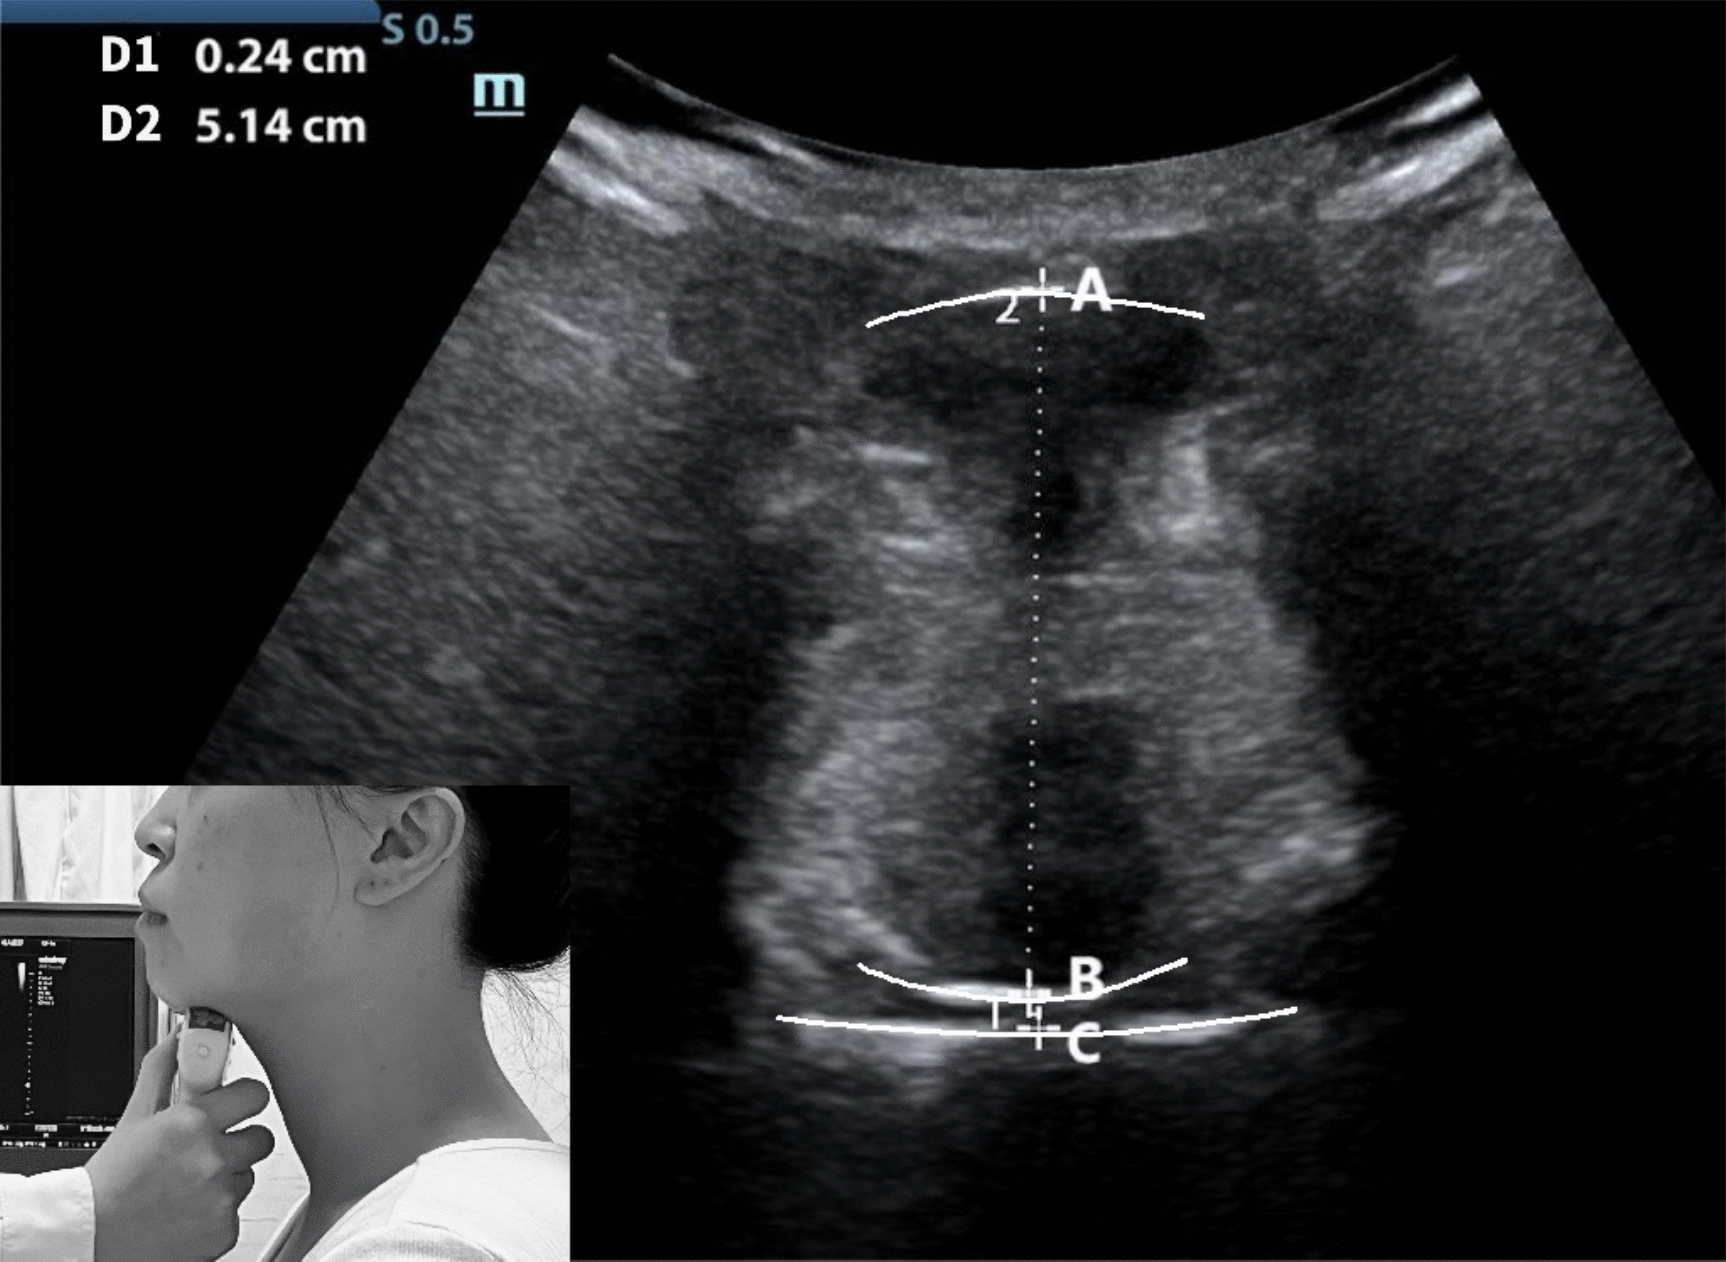

The participants were asked to be seated comfortably and look straight ahead in their habitual position; this involved ensuring no support was provided for their back while maintaining a chair height of 42 cm. The evaluator used Mindray ultrasound, UMT-500, and convex array probe C5-1s, Shenzhen Mindray Biomedical Electronics Co., Ltd. Initially, the probe was positioned at the anterior region of the subject's mandibular floor, aligning with its long axis, before gradually moving toward the hyoid bone. The short axis was placed between the posterior aspect of the tongue and the upper palate, enabling the measurement and documentation of tongue-palate distance. Screenshots were captured to measure and record tongue thickness (Fig. 1). The ultrasound mode was set to a frequency of 5 MHz and a depth of 8 cm. Two evaluators performed the measurements twice for the assessment of both intra-evaluator and inter-evaluator reliability. The mean values were derived for each evaluator, and data from the previous and subsequent evaluations were considered for assessment of the internal reliability between different evaluators (Evaluator A and Evaluator B). The interval between the two evaluations was 1 week, and a dedicated person recorded the data. The measurement indicators were tongue-palate distance and tongue thickness.

Fig. 1.

Ultrasound image of the tongue body scanned on the frontal plane. A Base tongue side bottom; B dorsal side of tongue; C palate surface. AB: tongue thickness, BC: distance between the tongue and palate

Tongue-palate distance: The distance between the tongue’s upper surface and the hard palate [23], in centimeters.

Tongue thickness: The vertical distance from the surface of the hyoid muscle to the back of the tongue [24], in centimeters.